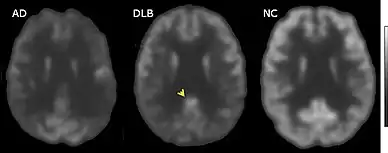

PET or SPECT imaging can be used to detect reduced dopamine transporter uptake and distinguish AD from DLB.[57][149] Severe atrophy of the hippocampus is more typical of AD than DLB.[150] Before dementia develops (during the mild cognitive impairment phase), MRI scans show normal hippocampal volume. After dementia develops, MRI shows more atrophy among individuals with AD, and a slower reduction in volume over time among people with DLB than those with AD.[33] Compared to people with AD, FDG-PET brain scans in people with DLB often show a cingulate island sign.[33]